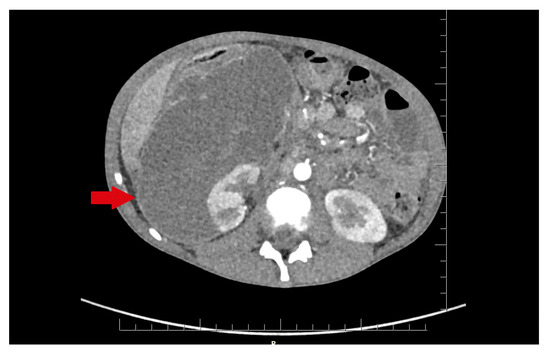

In the infectious disease ward, COVID-19 was excluded. During hospitalization, the patient developed acute abdominal symptoms. The acute condition of the boy appeared suddenly. Results of laboratory tests showed deviations in white blood cells (WBC) = 11.89 × 103/µL, and hemoglobin (HGB) = 6.9 g/dL, with hematocrit (HCT) = 20.6%. The inflammatory markers were elevated. Urinalysis showed 75 mg/dL of proteins. The ultrasound of the abdomen and computed tomography were performed. The diagnosis was unclear. Inflammation, abscess, cyst, and abdominal tumor were suggested. In the computed tomography (CT), the lesion had dimensions: 11.1 × 8.2 × 25 cm (Figure 1 and Figure 2).

Figure 1. The lesion of unknown character in the area of the right kidney, shown in the transverse plane of the CT scan. The lesion is marked by an arrow.